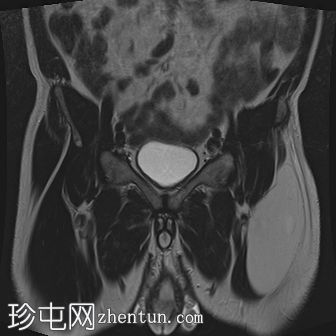

冠状位

T2加权像

左侧股直肌近端至中段肌纤维内可见一长条状、边界清晰的肌内肿块,其大小约为:头尾径14.4 cm,横径6.6 cm,前后径2.7 cm。

该病灶在所有序列上均呈脂肪信号,T1加权像上呈高信号,脂肪抑制像上信号完全抑制(假性高信号)。

未见厚间隔、结节状结构或非脂肪成分。